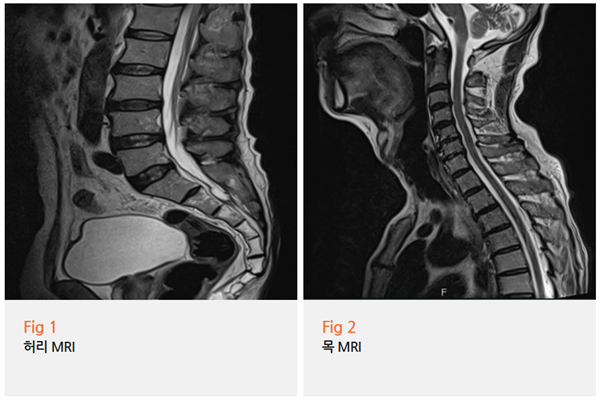

MRI 검사로 구조적 문제 확인

근전도검사로 신경 전도 속도 측정

혈액검사로 염증 수치와 영양 상태 파악

특히 근전도검사에서는

신경이 얼마나 손상되었는지,

어느 부위가 가장 심한지 정확히 알 수 있거든요.

이분의 경우 예상대로

손가락 끝과 발가락, 발목 주변 신경이

심각하게 손상되어 있었습니다.